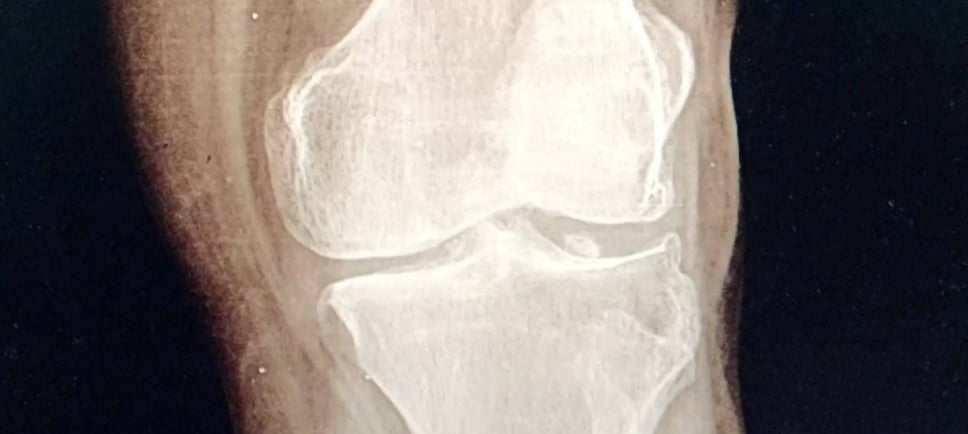

En muchos casos se solicitan estudios de imagen, como radiografías, ultrasonido o resonancia magnética, que permiten evaluar las estructuras internas de la articulación y confirmar el diagnóstico.